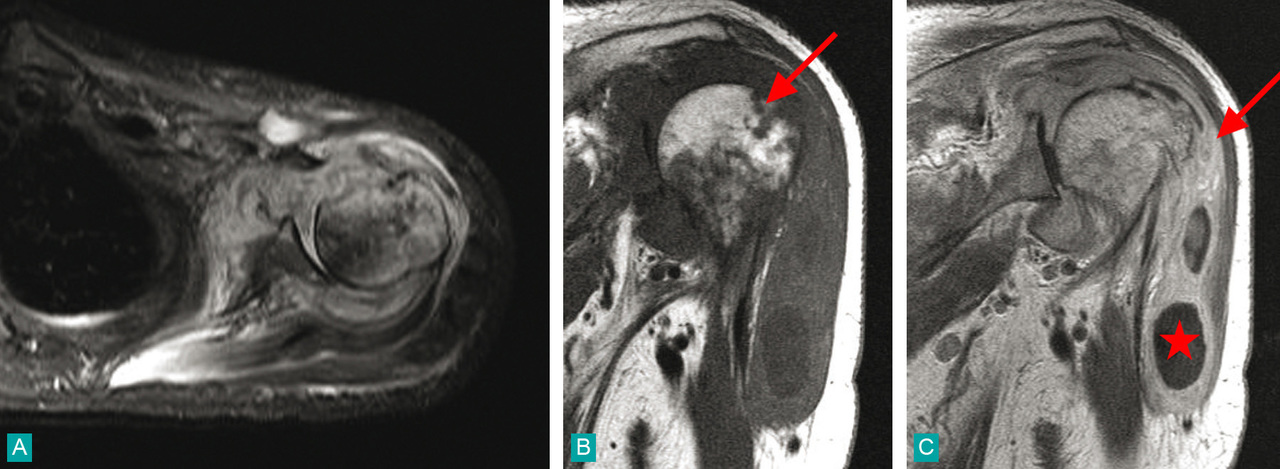

Imagerie par résonance magnétique d'une arthrite staphylococcique de l'épaule gauche :A. Coupe axiale de l'épaule gauche en STIR : importante synovite en hypersignal.B. Coupe frontale en T1 : hyposignal hétérogène de la métaphyse humérale avec épanchement dans la bourse sousacromiale (flèche).C. Même coupe après injection de gadolinium : prise de contraste de la synoviale et collections en hyposignal dans la bourse sous-acromiale (étoile).